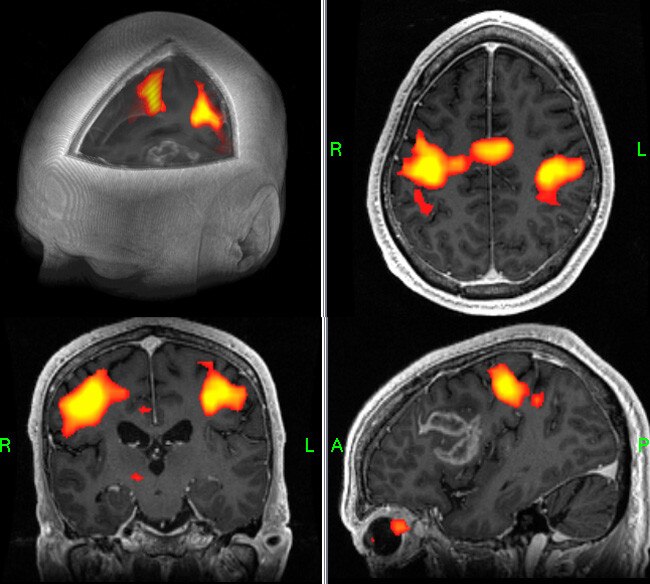

• Auf dem strukturellen Bild mit 2D- oder 3D-Darstellung überlagerte Anzeige von funktionellen Daten. Einfügen von Beschriftungen oder Ändern der Farbe und Opazität